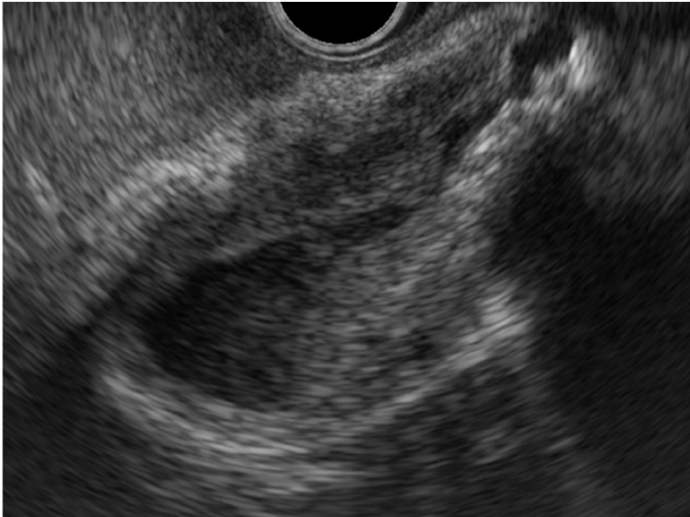

O Papel da Endoscopia

Para o gastroenterologista, a endoscopia, particularmente a ecoendoscopia (EUS), desempenha um papel indispensável. A EUS permite uma avaliação detalhada do parênquima pancreático, identificando achados sugestivos como o aumento hipoecoico difuso. Sua função mais crítica, no entanto, é a aquisição de tecido por punção ecoguiada, que é essencial para obter o diagnóstico histológico e, principalmente, para diferenciar a PAI de um carcinoma pancreático.

Fonte da imagem: Mendoça EQ. Colangite por IgG4 como diagnóstico diferencial do colangiocarcinoma hilar. Endoscopia Terapeutica 2023, Vol 1. Disponível em: https://endoscopiaterapeutica.net/pt/colangite-por-igg4-como-diagnostico-diferencial-do-colangiocarcinoma-hilar/

• A EUS com Biópsia é fundamental: A ecoendoscopia com punção por agulha é a ferramenta mais poderosa para diferenciar a PAI tipo 1 focal do câncer de pâncreas, uma etapa indispensável no diagnóstico.